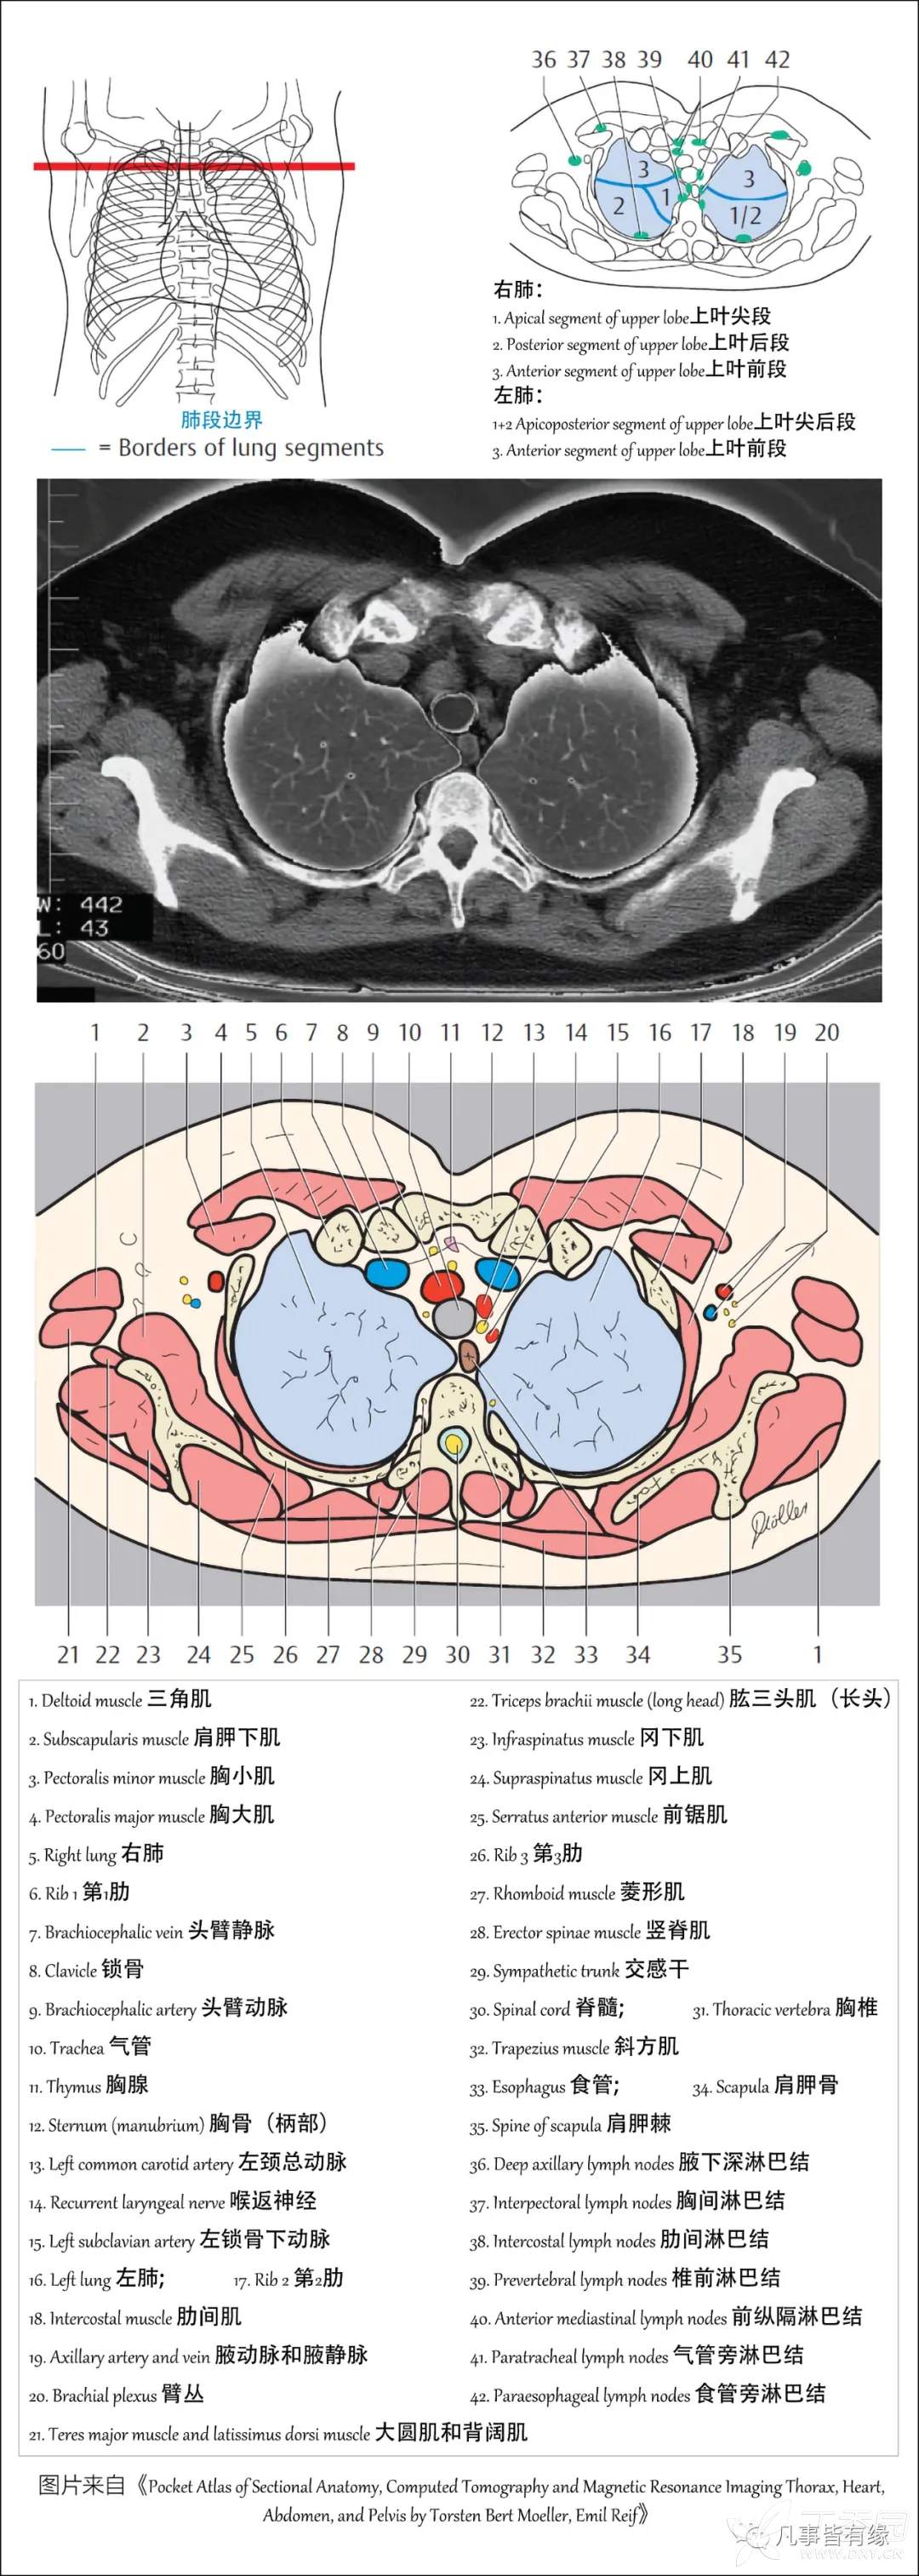

(一)胸部CT轴位断层解剖:

右肺(RightLung)

1.Apical segment of upper lobe 上叶尖段

2.Posterior segment of upper lobe 上叶后段

3.Anterior segment of upper lobe 上叶前段

4.Lateral segment of middle lobe 中叶外段

5.Medial segment of middle lobe 中叶内段

6.Superior segment of lower lobe 下叶上段

7.Medial basal (cardiac) segment of lower lobe 下叶内底(心)段

8.Anterior basal segment of lower lobe 下叶前底段

9.Lateral basal segment of lower lobe 下叶外底段

10.Posterior basal segment of lower lobe 下叶后底段

左肺(LeftLung)

1+2Apicoposterior segment of upper lobe 上叶尖后段